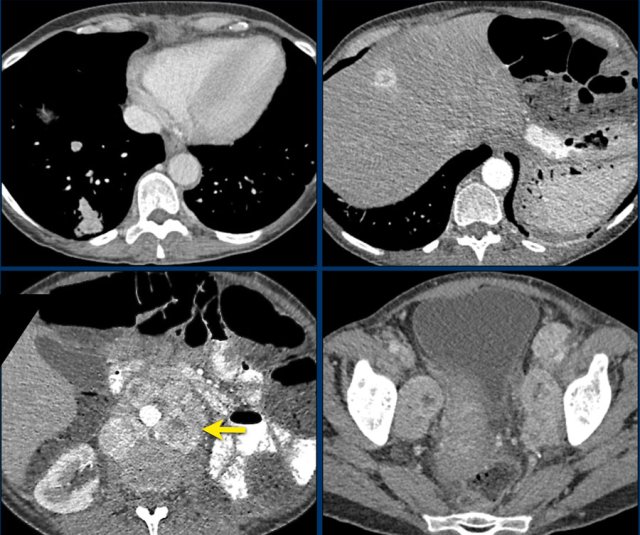

Axial and coronal CT images in a patients with a right adrenal carcinoma and extensive IVC invasion.

The coronal image also shows tumor extension into the right renal vein.

Axial and coronal CT images of another patient with an adrenal carcinoma with extensive IVC invasion (yellow arrow).

IVC and renal vein tumor invasion are seen in up to 20% of patients.

Here a large right adrenal adrenal carcinoma with extensive abdominal and mediastinal para-aortic lymph node metastases at the time of diagnosis.